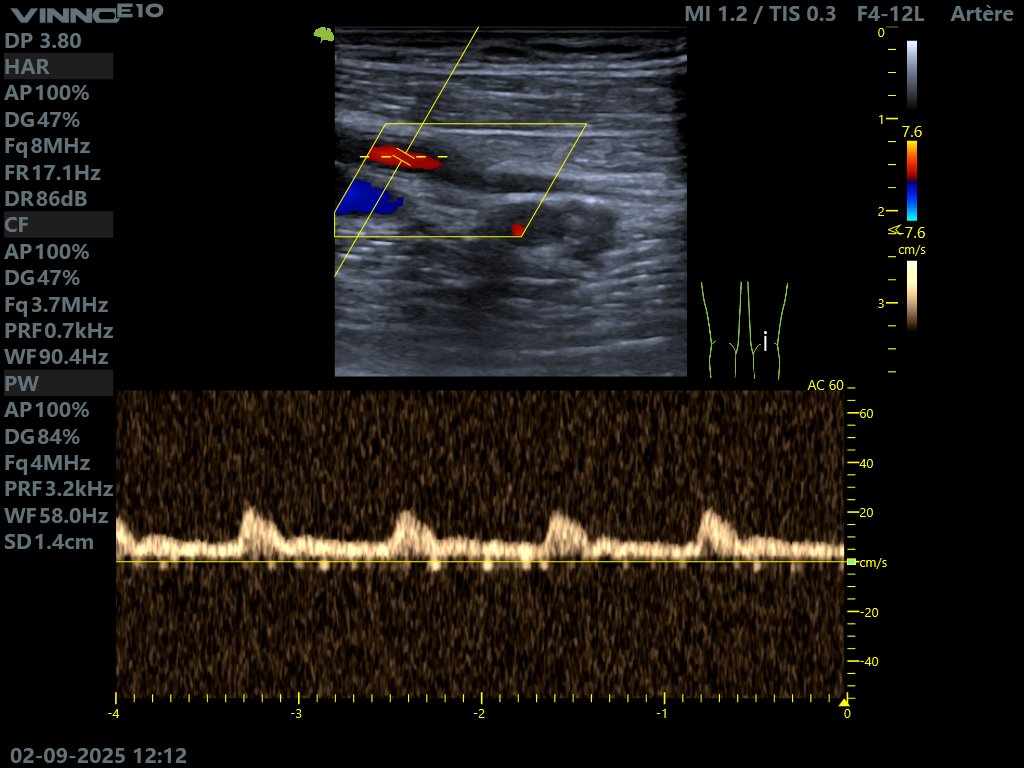

@tayfou La fémorale superficielle a un flux triphasique normalement, en absence de sténoses ou d'amortissement.

Le flux biphasique est celui de la fémorale profonde.

Belle icono mon frère

@kaddourkardio

Je sais que c'est au niveau de la female